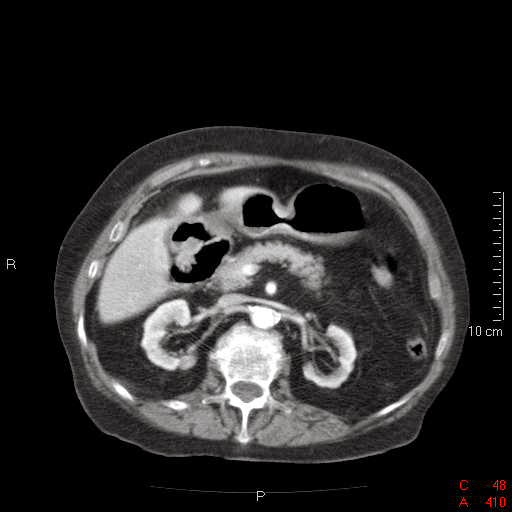

Contamos con radiografía de abdomen en bípedes ración como muestra el nivel en la cámara gastrica. Además, probablemente ante ante la sospecha de obstrucción intestinal, se practica TC de abdomen con contraste intravenoso con adquisición en fase portal, mostrándose reconstrucciones axiales a distintos niveles.

ResponderEliminarConfirmamos el hallazgo al que hacía referencia el doctor Gago en la radiografía de aire en la vía biliar (el aire se localiza en el centro del pare quina, no extendiéndose hasta la periferia, en cuyo caso hablaríamos de gas en la porta,sirviéndonos este dato para hacer la diferenciación radiologica)

Además, se confirma la presencia de dilatación de asas de intestino delgado, concretamente duodeno y yeyuno (no tengo la certeza de que también haya asas ileales dilatadas), observándose en las últimas un engrosamiento mural concéntrico, con discreto realce con el contraste y objetivandose una formación redondeada, de densidad calcio, en el punto de cambio de calibre de las asas. Por todo ello, consideró que se trata de un ileo biliar: obstrucción intestinal por una litiasis biliar que ha sido expulsada a través de la vía biliar, atravesando la papila y quedando impactada en el intestino delgado provocando un cuadro obstructivo.

Queria comentar hallazgos que se aprecian en la tomografia, incidentales dado que no tienen relación con la patologia aguda de la paciente. Un bazo accesorio, y una disminución del parenquima renal compatible con cierto grado de atrofia , hallazgo que se correlaciona con el antecedente de la paciente de insuficiencia renal cronica.

ResponderEliminarLa tríada de Rigler, como comentó la Dra. Buitrago, consiste en dilatación de intestino delgado con niveles hidroaéreos, litiasis biliar ectópica y aerobilia. Esta tríada aparece en el 40-50% de los casos en la radiografía convencional y es considerada patognomónica de íleo biliar. En nuestro caso no se identifica la litiasis ectópica en las imágenes de radiografía convencional. Sin embargo, en la TC se ve claramente en el yeyuno la litiasis que provoca la obstrucción. En las imágenes de TC hay otra litiasis. ¿Dónde se encuentra?